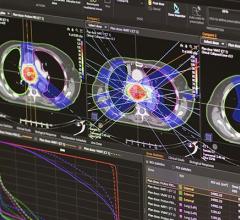

December 11, 2008 - The first patient to be treated clinically with a new treatment planning system for proton radiation therapy developed by RaySearch took place at Uppsala University Hospital in Sweden.

The system is integrated in the Oncentra MasterPlan treatment planning system from RaySearch's partner Nucletron. The University Hospital treats more than 100 cancer patients annually with proton therapy at the The Svedberg Laboratory and the system will be used for all proton treatments in the future.

"The new treatment planning system saves substantial time with its user-friendly tools providing us with various optimization alternatives and the possibilities of making fine adjustments. The dose calculations are exact and optimized to the clinical reality. In addition to the concise presentation of treatment plan data, filter and field shapes are visualized graphically in a clear and pleasant manner," said Christina Vallhagen Dahlgren, senior hospital physicist, proton therapy at the University Hospital.